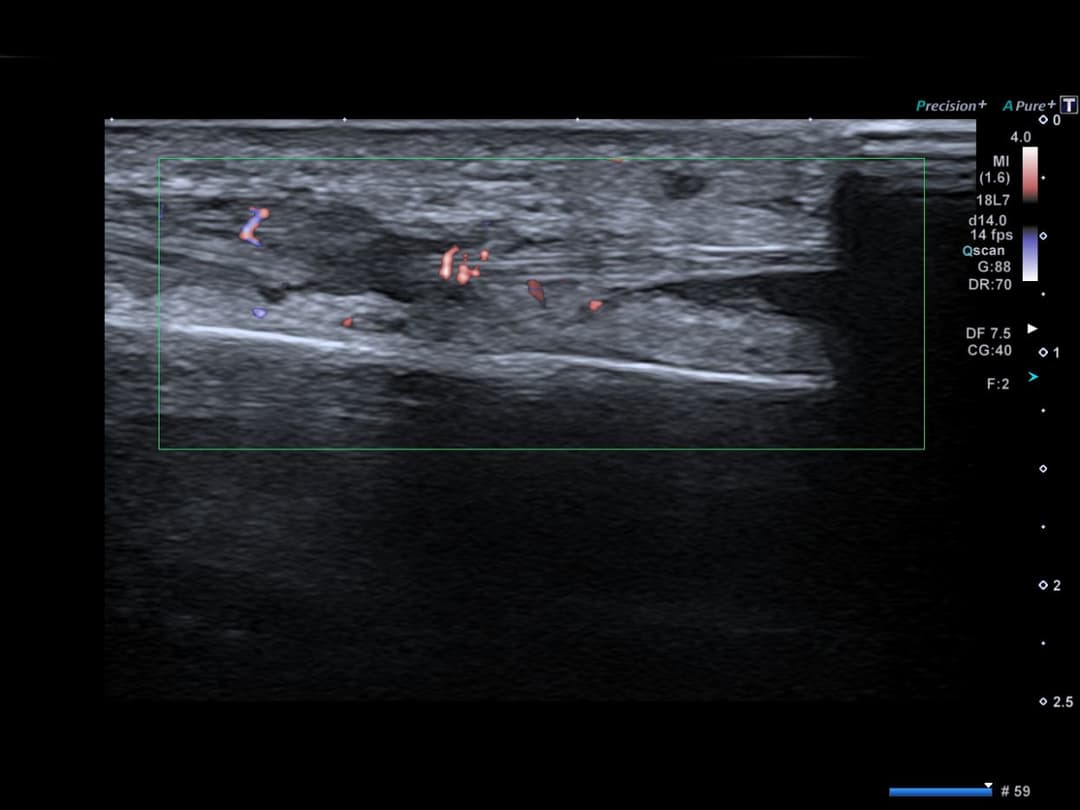

Congestion œdémateuse des parties molles en regard du croisement tendineux entre d'une part les tendons court et long extenseurs du carpe et d'autre part les tendons du premier compartiment tendineux (court extenseur du pouce et long abducteur du pouce).

Légère lame d'épanchement dans la gaine synoviale de ces tendons en distalité de la zone conflictuelle.

Hyperhémie modérée en Doppler couleur.

Congestion œdémateuse en regard de la zone de croisement proximal

Discret épanchement dans la gaine synoviale

Hyperhémie modérée en Doppler couleur